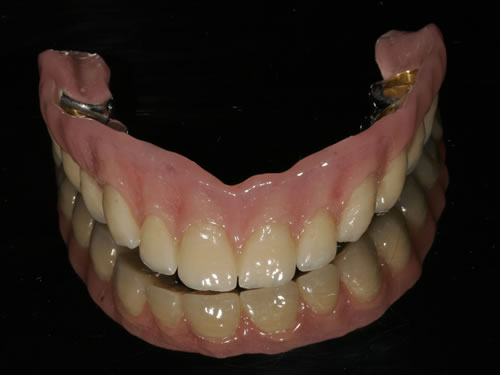

Für den zahnlosen Ober- und Unterkiefer werden dies häufiger Stegkonstruktionen oder Teleskopversorgungen sein (Abb. 8.8 bis 8.16).

Nach 3 Monaten kommt Frau W. zur prothetischen Versorgung. Es wurde wieder ein Kostenplan erstellt. Die erste Behandlung besteht in der Eröffnung der Schleimhaut über den künstlichen Zahnwurzeln. Dies wird in örtlicher Betäubung vorgenommen, anschließend ein Abdruck gemacht und in jedes Implantat ein kleiner Pfosten eingeschraubt, der verhindern soll, dass sich die Schleimhaut wieder schließt. Der Zahnarzt hat die Prothese ausgeschliffen, sodass sie jetzt wieder eingesetzt werden kann. Frau W. spürt, dass sie jetzt schon einen besseren Halt hat. Bereits nach 3 Tagen ist die nächste Anprobe. Der fertige Steg wird eingesetzt. Nun werden nur noch die Halteklammern in die Prothese eingearbeitet. Dazu muss die Prothese einen Tag in das zahntechnische Labor. Am Abend ist es dann soweit. Die Prothese wird eingesetzt. Bereits beim ersten Versuch, sie herauszunehmen, bemerkt Frau W. den guten Halt. Eine Zahnarzthelferin zeigt ihr, wie der Steg und die Prothese gepflegt werden müssen. Die erste Kontrolle soll bereits nach 14 Tagen durchgeführt werden, um zu gewährleisten, dass alles richtig gemacht wird. In den ersten Tagen muss Frau W. noch etwas vorsichtig beim Essen sein, damit sich die künstlichen Zahnwurzeln an die neue Belastung anpassen können.